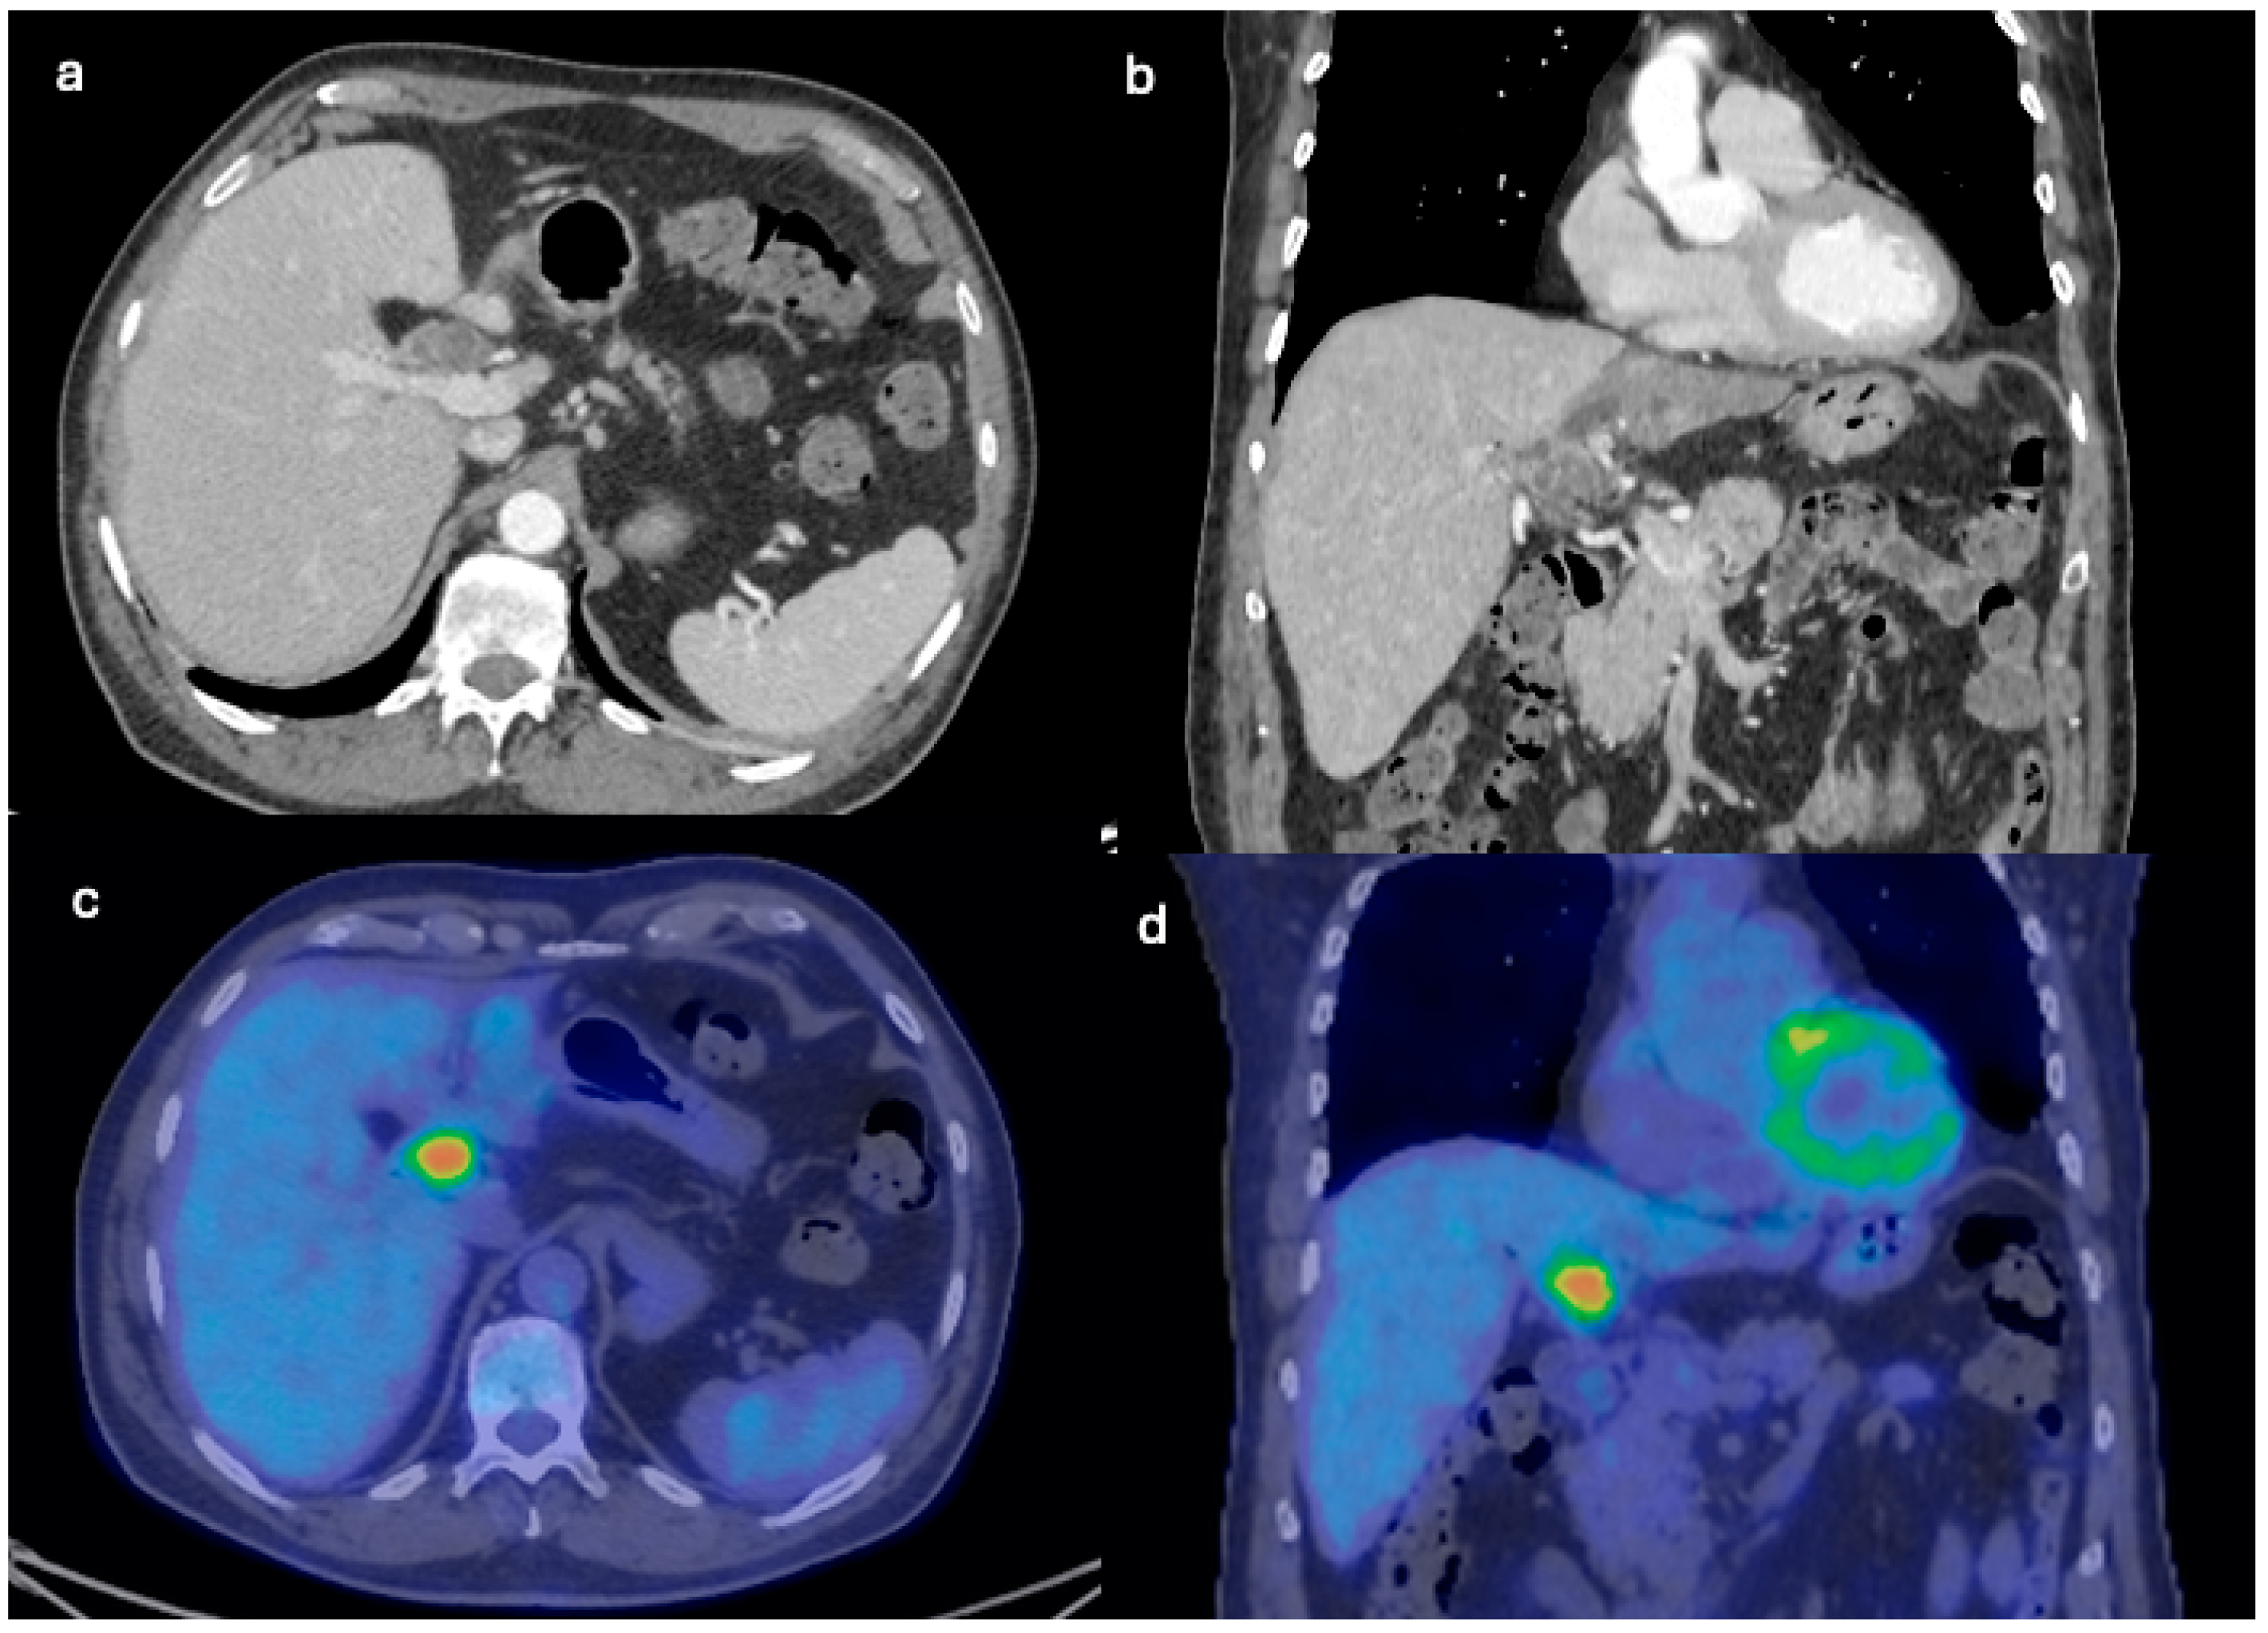

3. Case Report 2

| Initial Diagnosis | Suspected hydatid cyst | Simple cyst, later adenocarcinoma with metastases |

| Diagnostic Methods | MRI, MRCP, ERCP, histopathological examination | CT, MRI, laparoscopic liver biopsy, histopathological examination |

| Tumor Characteristics | Large cystic mass, thin walls, internal septa, papillary projections, enhancing solid components | Large lesion in left hepatic lobe, hyperintensity in T2-weighted images, restricted diffusion, contrast enhancement |